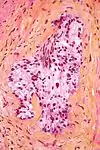

Micrograph demonstrating perineural invasion. HPS stain.